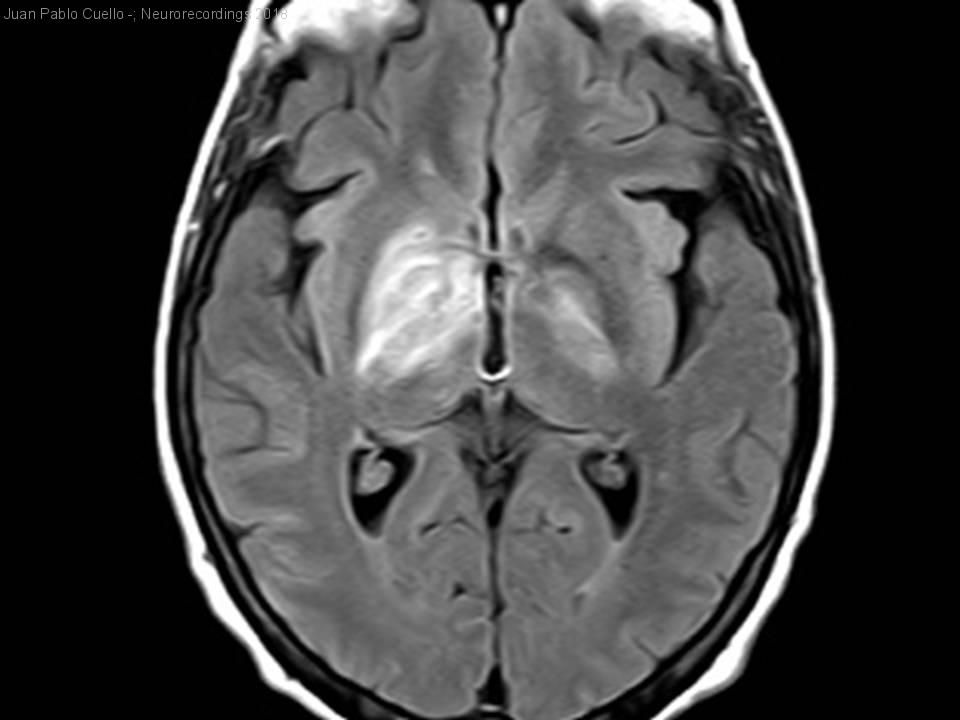

Coreoatetosis subaguda como forma de presentación de un linfoma cerebral primario

Mujer | 70 años

Diagnóstico final: Linfoma Cerebral Primario

Mujer 70 años con diabetes e hipertensión. Un mes previo al ingreso, consultó a raíz de un cuadro de mareo e inestabilidad, inespecífico y recibió tratamiento sintomático con Metoclopramide y Betahistina. Tras 2 semanas, consultó...